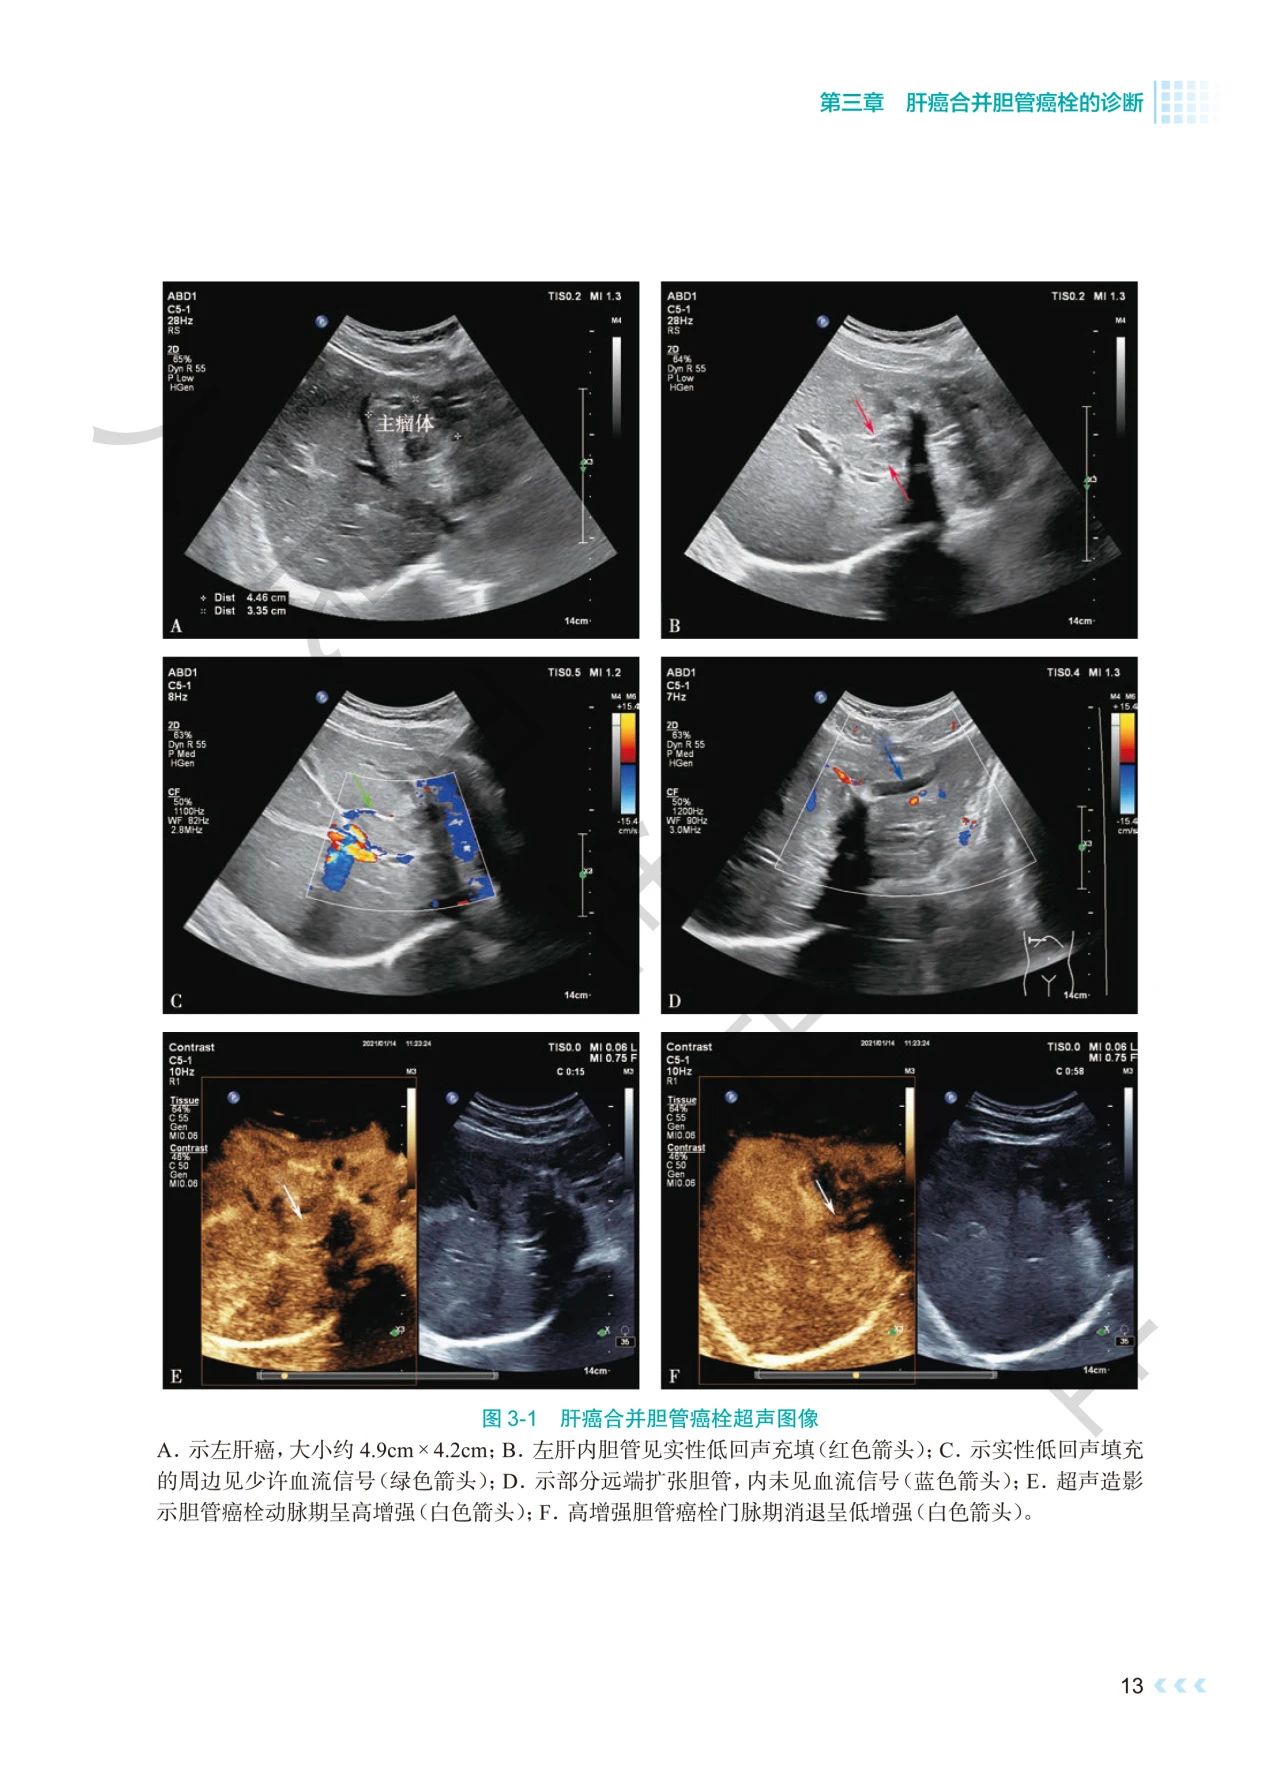

《肝癌合并胆管癌栓诊治》深入探讨了肝癌合并胆管

癌栓诊治领域的焦点问题。书中通过影像图、示意图

、手术图,详细阐述了不同分型胆管癌栓的影像学特

点及手术方式,提出q形胆总管切开取栓方法,强调解

本书通过丰富的示意图、影像图和手术图,对肝癌合

并胆管癌栓的分型、诊断策略、治疗方法等进行了深

入剖析,全面系统地总结了肝癌合并胆管癌栓领域的